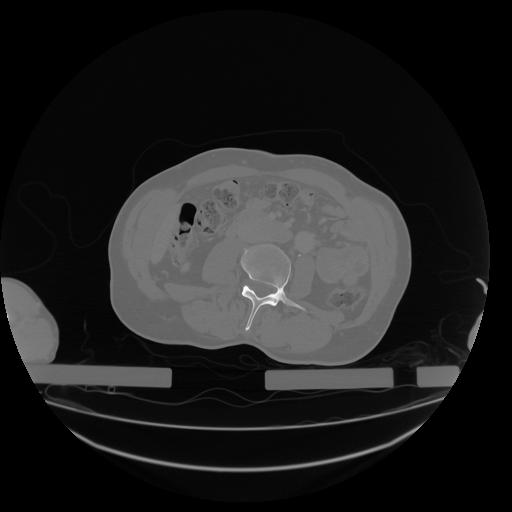

34 CUERPO,CE,Vol,1.0,CUERPO,,